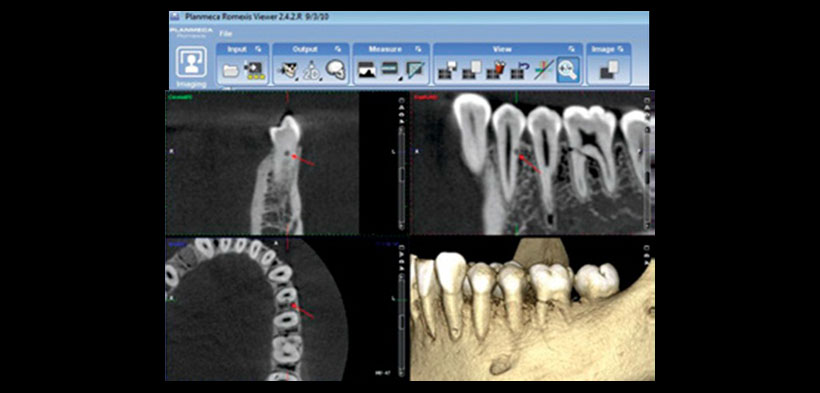

Fig. 1. Radiografía periapical digital de la pieza 3.4. Toma ortogonal (izquierda) y la correspondiente proyección mesioangulada (derecha) de la pieza 3.4 con sospecha de reabsorción radicular externa (RRE).

Fig. 2. Equipo Planmeca, Software Romexis Viewer. Tomografía computarizada cone beam (TCCB) muestra la vista axial, coronal, sagital, y la reconstrucción tridimensional; se logra realiza el diagnóstico de reabsorción radicular externa (RRE) en la pieza 3.4 (distal, flecha).